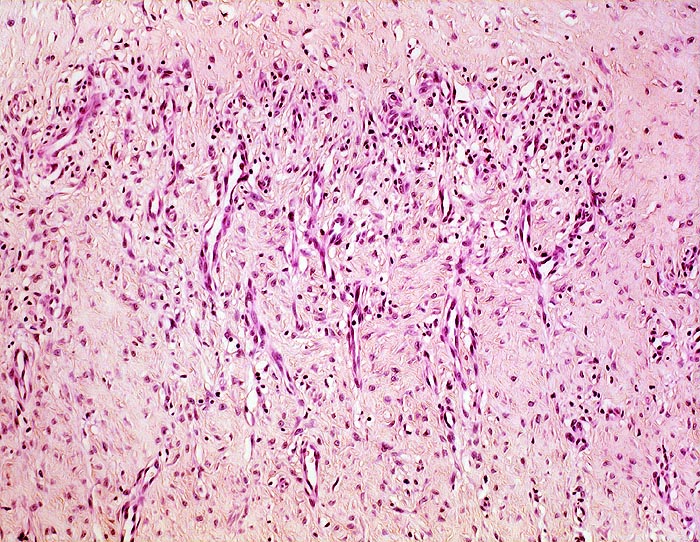

Organisationsgewebe der Bursawand mit neugebildeten kapillären Gefässen zwischen fibroblastenreichem Bindegewebe. Lockere, vorwiegend perivaskuläre lymphohistiozytäre Infiltrate

Das Granulationsgewebe organisiert von innen her die nach mechanischer Belastung immer wieder von Neuem gebildeten Fibrinexsudate. Später wird das Granulationsgewebe ersetzt durch Narbengewebe.